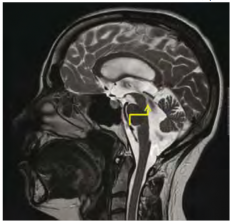

למבוגרים אשר מפתחים הידרוצפלוס בשנות חייהם המתקדמות יש כנראה יותר מנגנוני פיצוי אשר מונעים עלייה מסוכנת בלחץ התוך-גולגולתי מאשר לילדים וההידרוצפלוס מתפתח אצלם יותר באיטיות. הידרוצפלוס כרוני הוא מצב המוגדר הדמייתית בבדיקות טומוגרפיה ממוחשבת (CT ,Computed Tomography) ו/או תהודה מגנטית (MRI ,Magnetic Resonance Imaging) על ידי אומדן הגדלת החדרים. אחד המדדים לגודל החדרים הוא Evans index, היחס בין רוחב הקרניים המצחיות לרוחבו המירבי של המוח. בהידרוצפלוס כרוני מדד זה יהיה גדול מ-0.3 (תמונה מספר 1). מדדים הדמייתיים נוספים הם הרחבת הקרניים הרקתיות, שינויי אות או בצקת סביב חדרי המוח ושינויים באות הזרימה בתעלה (Aqueductal/fourth ventricular flow void) (תמונה מספר 2), בנוכחות לחץ CSF תקין או מעט גבוה. התמונה ההדמייתית מלווה בהתפתחות של תסמינים קליניים דומים, ללא קשר לגורם הראשוני.

| MRI | דימות מבני | Flow void של התעלה או של החדר הרביעי | ||

| דימות תפקודי | נפח פעימה (Stroke volume) — מוגדר כממוצע נפח ה-CSF העובר דרך התעלה בסיסטולה ובדיאסטולה. נפח פעימה מעל 42 מיקרוליטר יכול לנבא שיפור בתר-ניתוחי | יכול לשמש כמדד מנבא תומך להצלחת הניתוח |